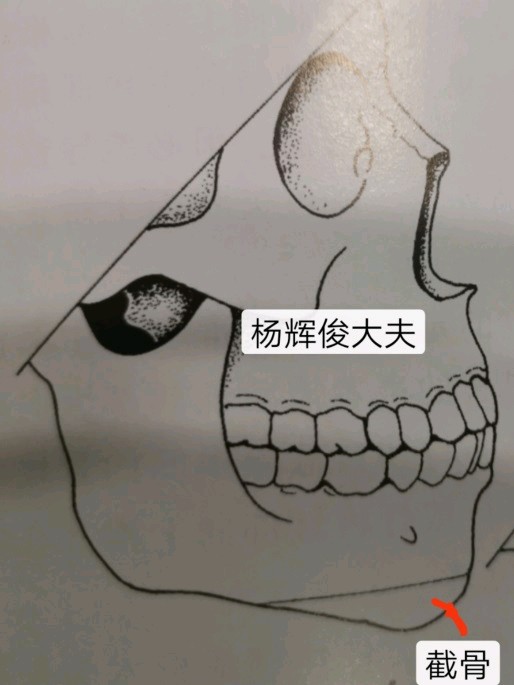

一、颏成形术

口内进路的水平截骨颏成形术是矫正各种颏部畸形的基本术式,无论是作为正颌外科的辅助手术,还是作为独立的面部整形美容手术,其应用越来越普遍。也是目前矫治各种颏部形态异常的最佳手术。

术式灵活多样:水平前徙式、缩短前徙式、缩短后退式、双台阶前徙式、铰链前徙式、植骨加高前徙式、水平移位式、水平旋转移位式、三角形骨段切除式、楔形骨段切除式、梯形骨段旋转移位式、颏部骨段加宽式、颏部骨段缩窄式、不需植骨的颏部加高式、颏部修正术等。